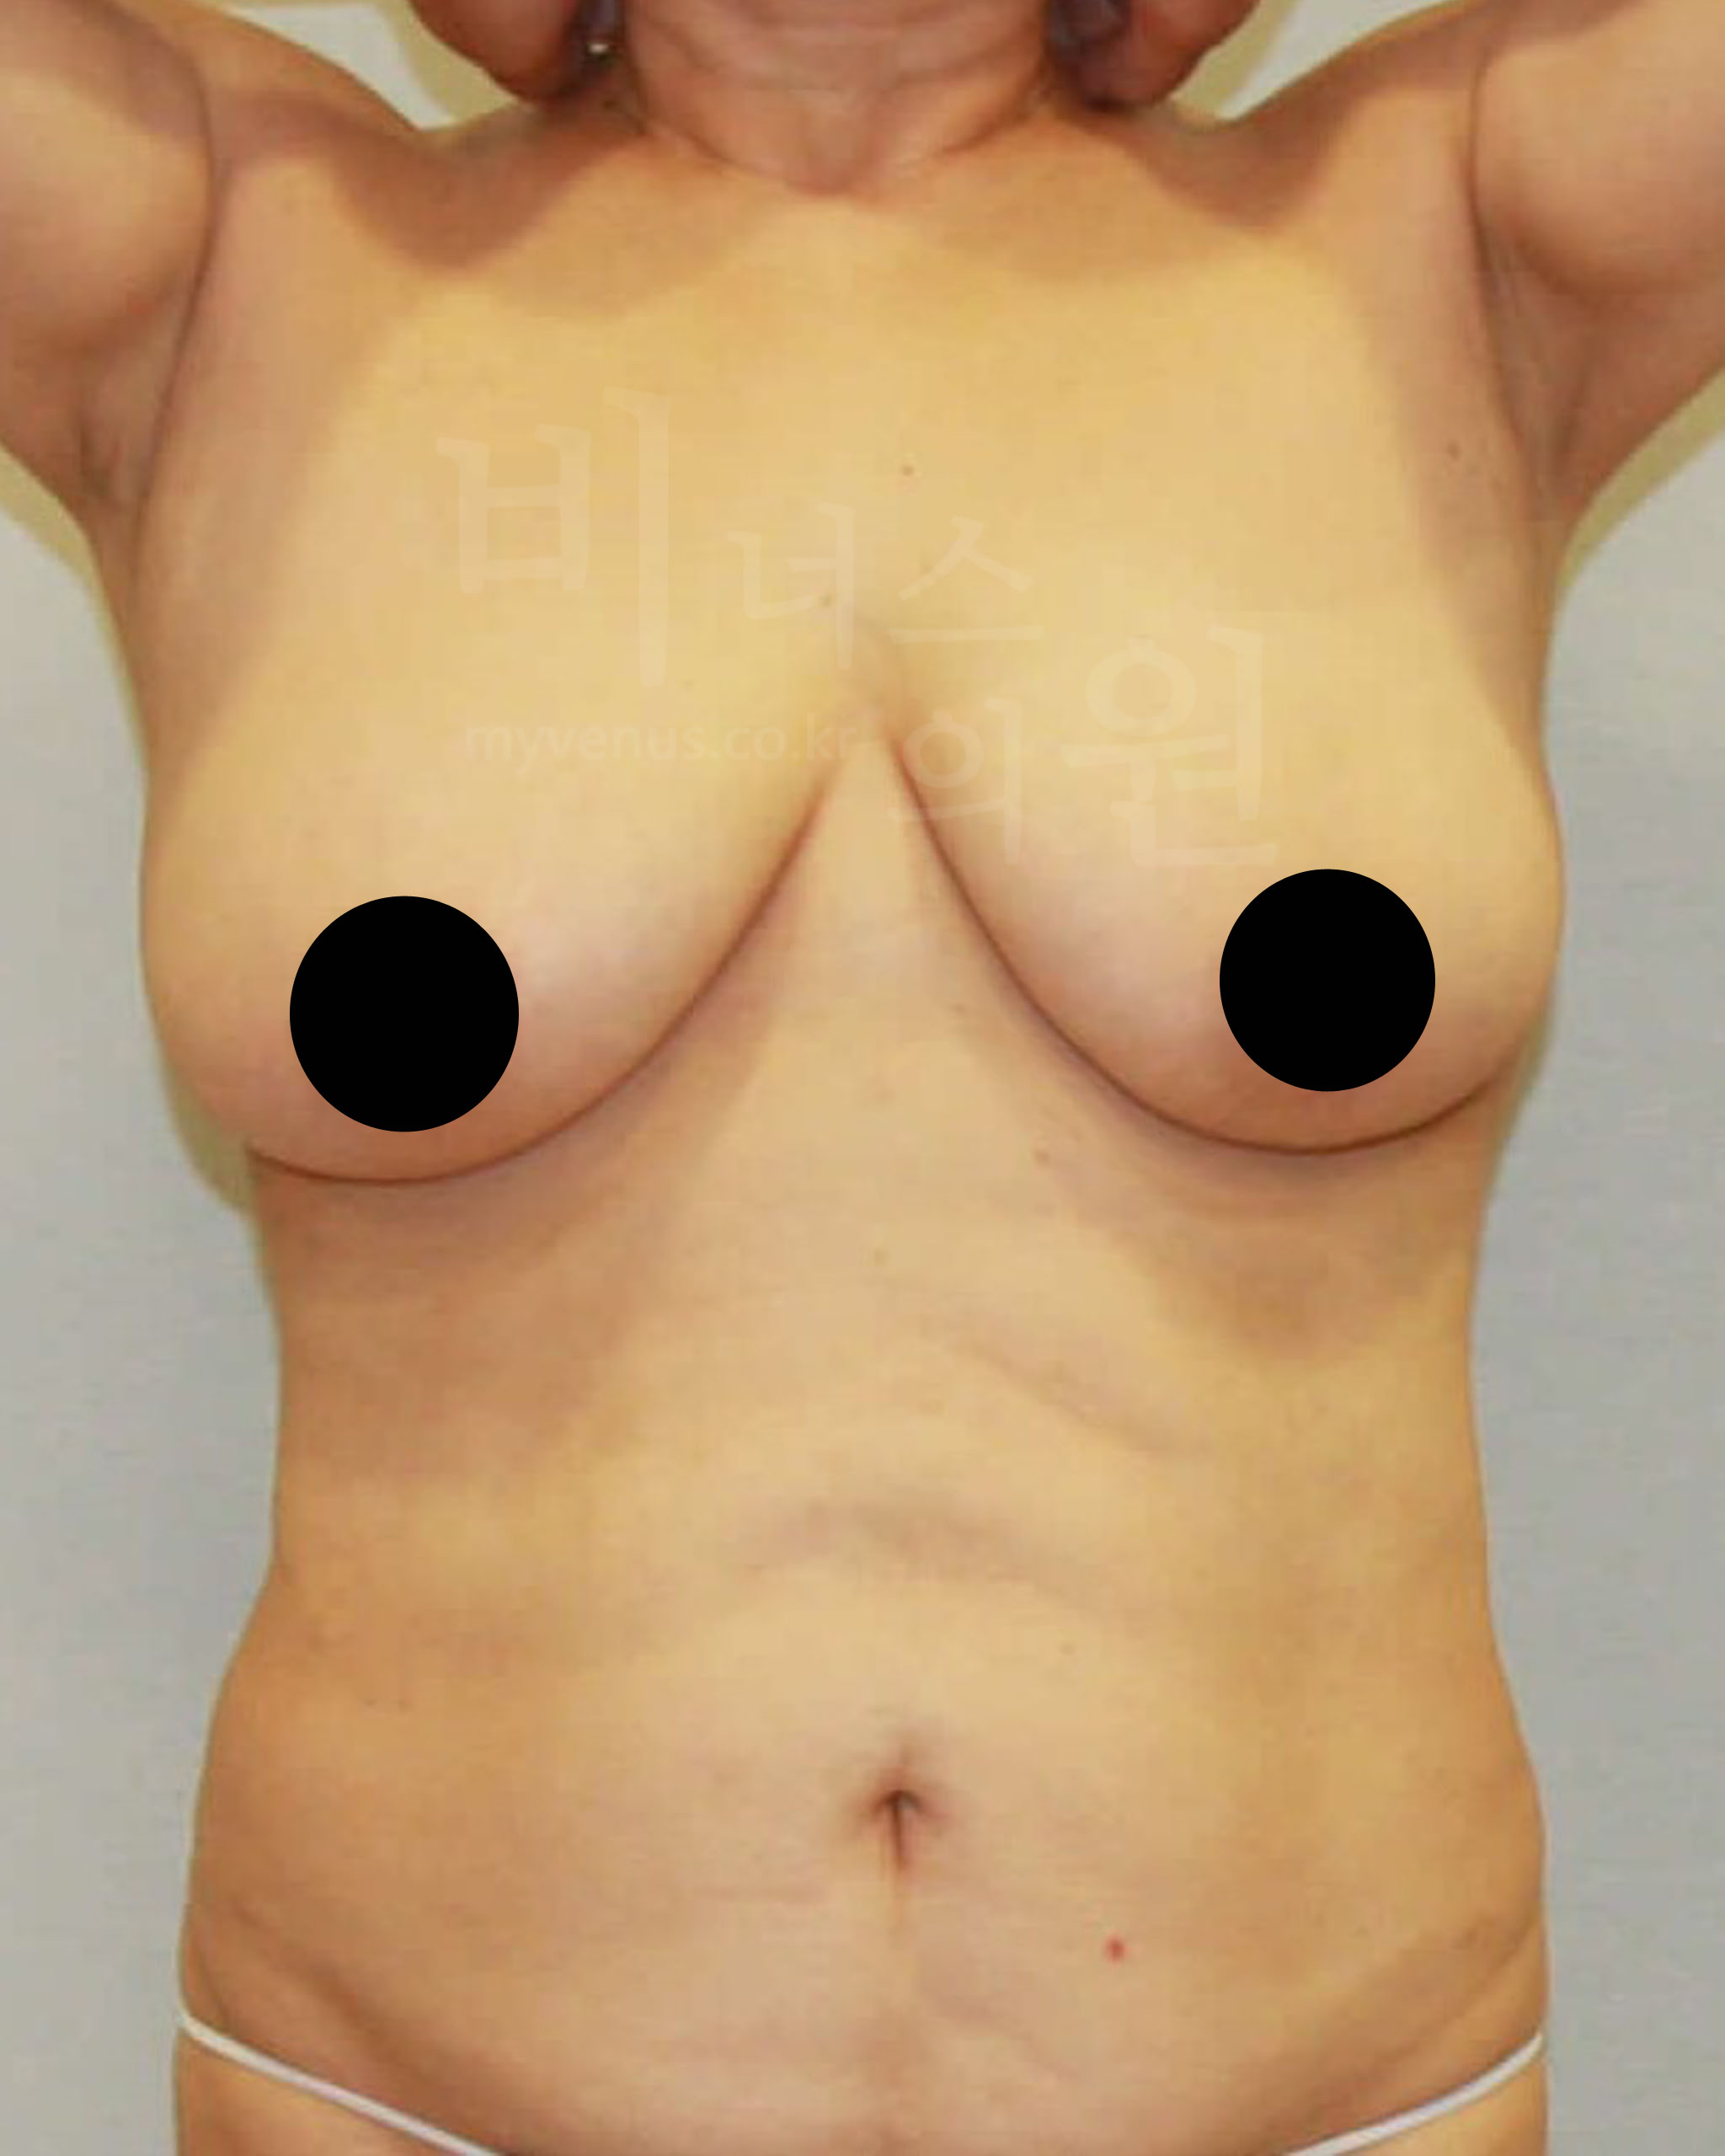

가슴축소 지방흡입 전 사진

탄력이 없어 힘 없이 가슴이 아래로 향한 모습

가슴축소 지방흡입 후 사진

피부 수축으로 리프팅과 탄력이 생긴 모습

가슴축 지방흡입은 절개를 하지 않아도 충분히 사이즈 감소와 처짐 없이 볼륨 업된 가슴으로 교정이 가능해요. 또한 유선을 건드리지 않고 지방만을 흡입하여 축소하기 때문에 젊은 여성분의 추후 모유수유에도 지장이 없어요. 멍, 붓기, 흉터, 부작용의 발생 없이 가슴이 자연스러운 모양으로 감소된 모습이에요.

수술 부위 - 가슴 축소, 부유방, 겨드랑이, 유방 옆구리 지방흡입

가슴축소 지방흡입 전 사진

처지고 무거워 밑으로 축 늘어져 있는 모습

가슴축소 지방흡입 후 사진

처지고 무거운 가슴이 교정된 모습

40대의 여성으로 사이즈 감소와 처짐의 교정을 위해 내원하셨어요. 탄력 있으면서 볼륨 있는 사이즈 감소를 원하셨어요. 가슴 축소, 부유방, 겨드랑이, 유방 옆구리 지방흡입으로 도움을 드리기로 했어요. 가슴 사이즈 감소로 무게감이 훨씬 줄어들어 보이며, 사이즈 감소와 탄력 있으면서 봉긋 업된 가슴이 되었어요.